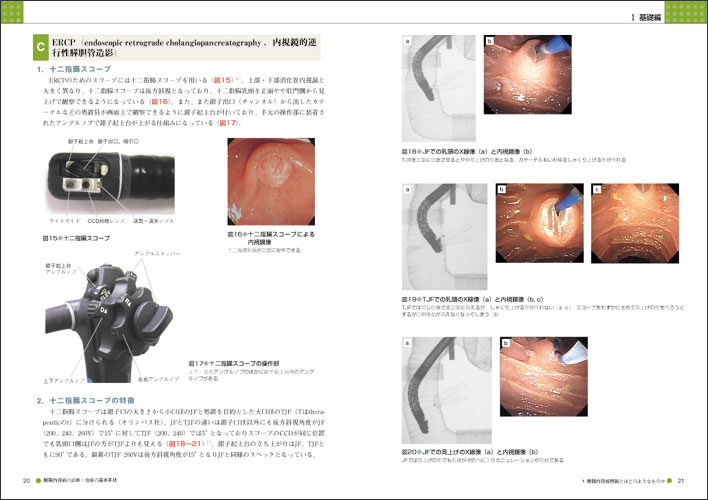

胆膵内視鏡の診断・治療の基本手技 第3版 | 糸井 隆夫 |本。胆膵内視鏡 診断・治療の基本手技 第4版 | 糸井 隆夫 |本 | 通販。胆膵内視鏡の診断・治療の基本手技 第3版 | 糸井 隆夫 |本。国産米粉のホットケーキミックス☆驚くほどもっちり☆MOLINAGA☆2袋セット。胆膵内視鏡 診断・治療の基本手技 第4版 - 羊土社。最先端治療 胆道がん・膵臓がん – 法研。裁断済(バラバラ)の本です。胆膵内視鏡の診断・治療の基本手技 第3版 - 羊土社。。胆膵内視鏡 診断・治療の基本手技 第4版 - 羊土社。胆膵内視鏡でサポートバンドを導入 - 事例紹介|Medicle。内視鏡センター|社会医療法人三栄会 ツカザキ病院。胆膵内視鏡の診断・治療の基本手技 改訂2版」付録DVD。胆膵内視鏡の診断・治療の基本手技 - 羊土社。裁断済みの為、状態が悪いとしていますが、書き込み等ございません。使い方の分かる方のご購入をお願いいたします。JDDWで売上1位を獲得した話題の新刊『これで完璧!胆膵内視鏡の